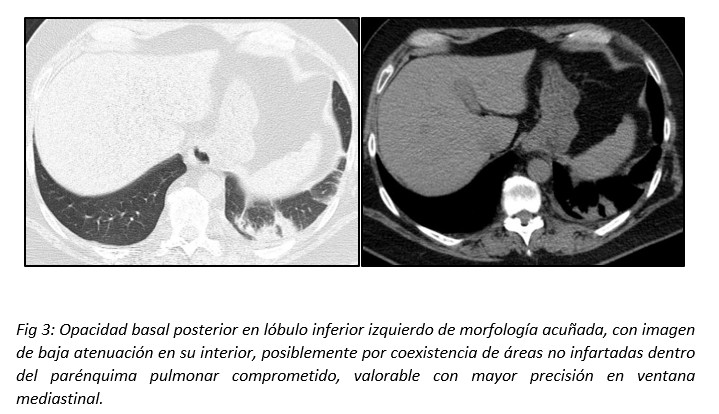

Las opacidades pueden presentar imágenes de baja atenuación en su interior, atribuibles a áreas no infartadas con parénquima pulmonar sano. Esta característica puede observarse con mayor precisión en la ventana mediastinal. Los sectores de baja atenuación dispersos dentro de la lesión también pueden ser un signo de necrosis o fruto de la distribución geográfica irregular de una hemorragia pulmonar focal en el sitio de isquemia.14(Fig 3)